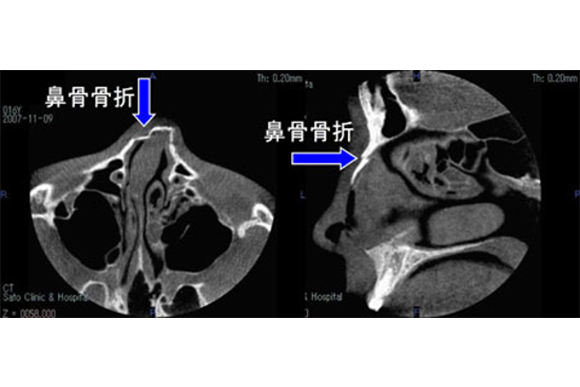

顔面打撲などで鼻に外力が加わると、鼻骨が骨折し変形の原因になることがあります。発症2週間以内は外来で局所麻酔下の整復が可能ですが、2週間を経過すると全身麻酔での整復手術が必要となり、その場合は高次機能病院へご紹介させて頂きます。